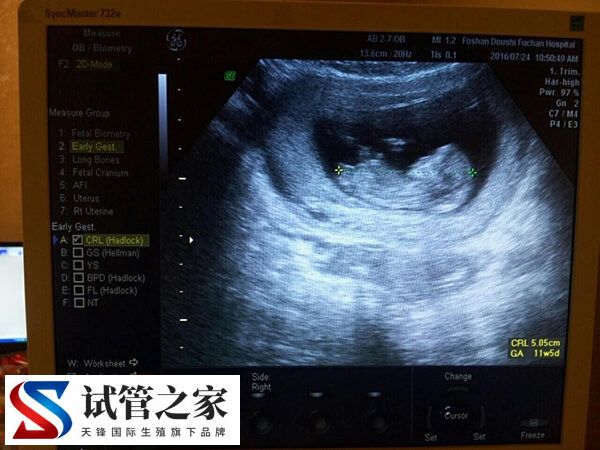

促排卵期间雌二醇600多却取了3个卵泡是怎么回事?

在促排卵期间,若是患者的雌二醇水平为600多,通常可以获得的成熟卵泡数量大约在4-6个,但如果患者只取了3个卵泡,可能是正常的,也可能是个体对促排卵药物的反应较差多是,或是存在卵巢过度刺激综合征的风险,对此建议患者继续与医生保持密切沟通,根据具体情况做出最适合的治疗决策。

雌二醇水平600多pg/mL却仅获得3个卵泡的原因,主要与个体生理差异、卵泡发育状态及促排反应特性相关,具体分析如下: